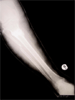

Post

Op

Ilizarov compression with fibular osteotomy

Progress

Progress : Healing nonunion and deformity corrected